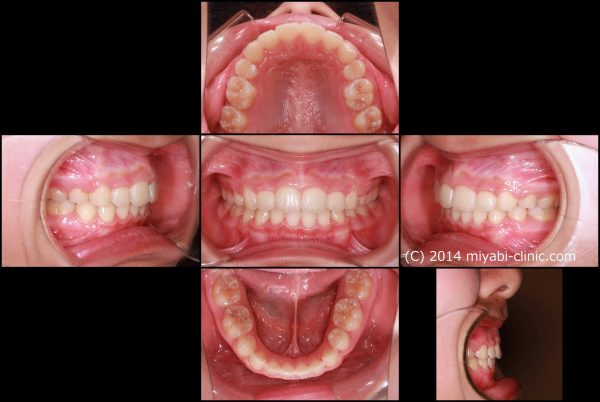

治療前後で前歯の傾斜がかなり改善しました。

レントゲン写真で確認しても上下の前歯は 大きく下がり、

前に飛び出していた上下の前歯の傾きが正常化しました。

上下の口唇もかなり下がりました。

口唇の飛び出した感じがなくなり、鼻の下、下唇の形が整いました。

治療途中で 「アゴが できた! 」と親御さんも喜んで頂けました (#^.^#)

歯ならび が変化したことで、上下の口唇が大きく下がり、あごのラインが綺麗になりました。

口もと の飛び出し感が 解消され、自然に お口が閉じられるように なりました。

口もとが上下ともに下がった効果で、鼻が高くなったかのように見えますね。(鼻の高さは変わりません)

”おとがい”の緊張感も解消し、口もとの ”もっさり感” が解消しました。

アゴの シワが完全に消失しました

自然に口が閉じられるようになり、口もと(鼻の下、下唇)の出っ張っている感じが解消しました。

口もとが 下がり、スッキリとした印象のお顔になりました。

前歯の 飛び出しが 解消し、”出っ歯” 感が解消しました。

前歯の出っ張りが解消し、スマイル ラインが整いました

13歳女性 叢生を伴う 上顎前突症 治療期間22か月 唇側矯正装置(ホワイトワイヤー)を使用した上下顎第一小臼歯抜歯治療 参考治療費 約67万円(消費税込み73万円) (精密検査から終了まで) 矯正治療に伴う副作用の歯肉退縮、知覚過敏、失活、歯根吸収などは認められませんでした。